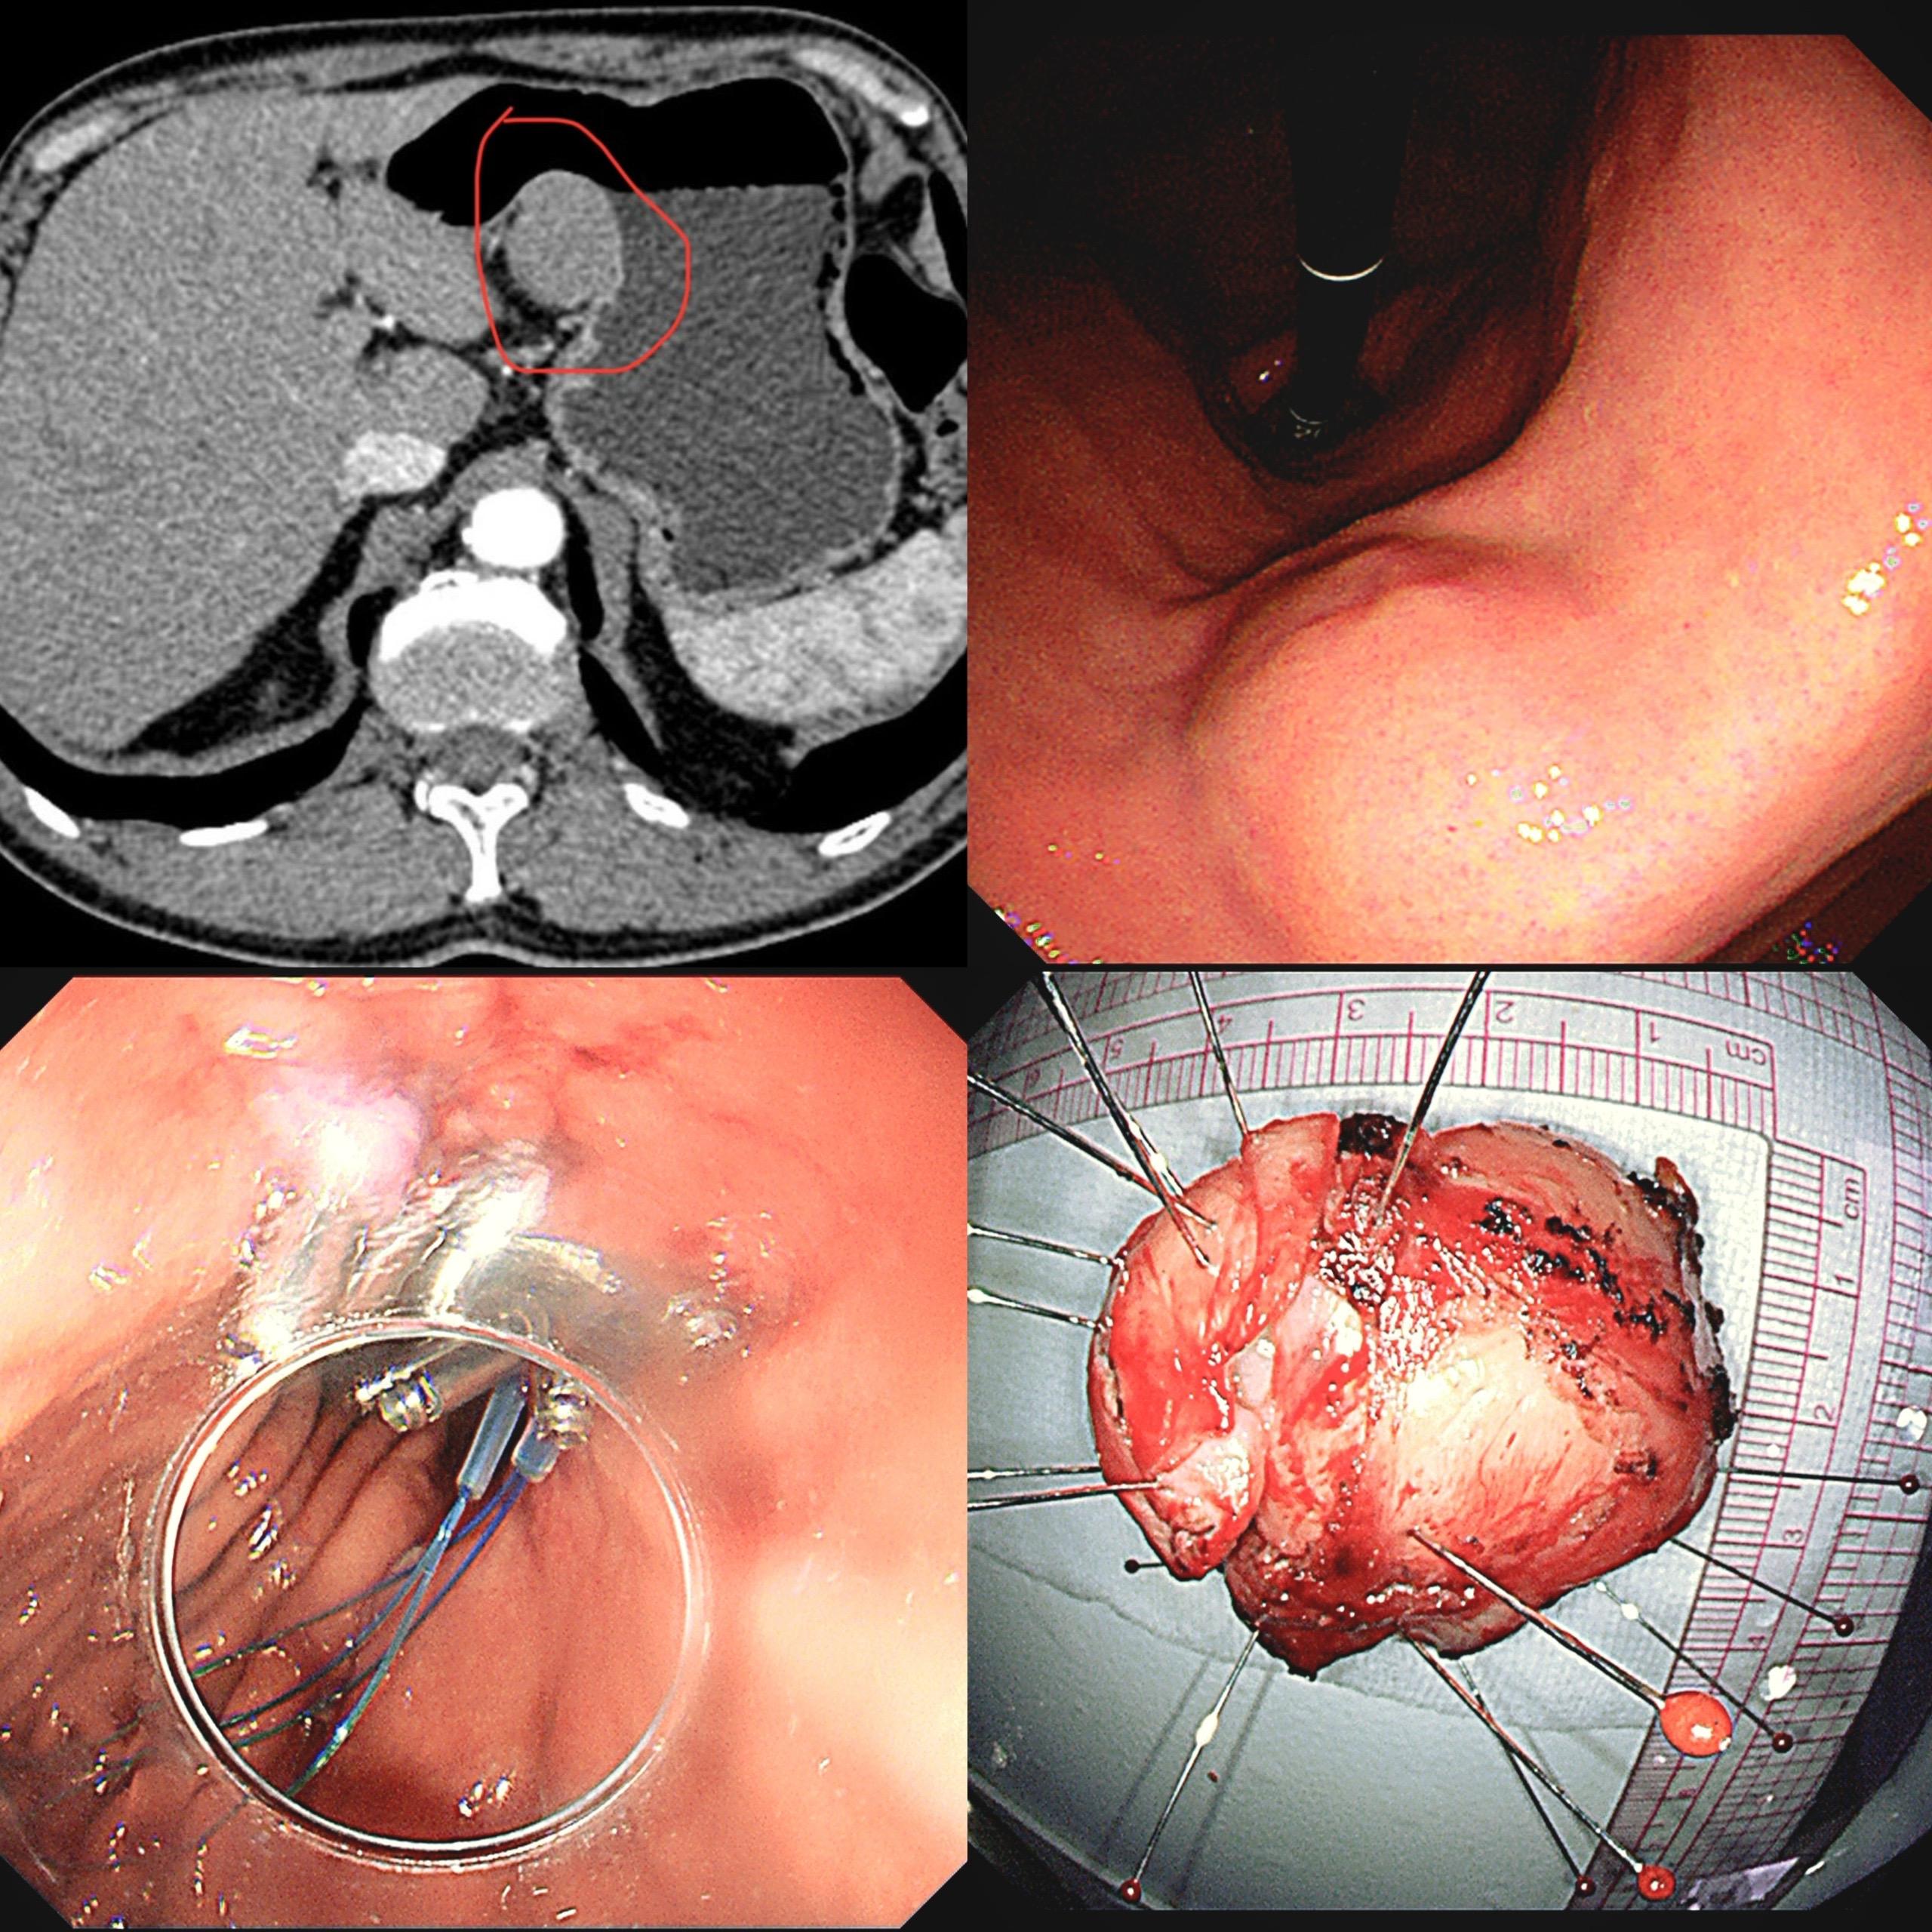

【精于术,简于形】 一例胃角间质瘤内镜下全层切除。 肿瘤虽小(2cm)...